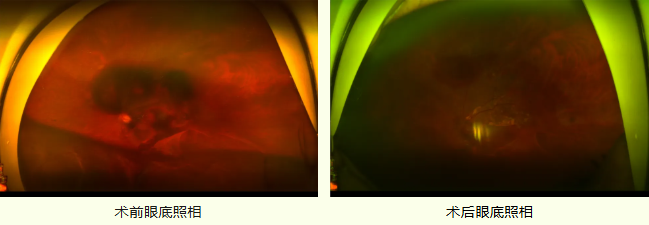

姜先生因“左眼视物不清半个多月,加重5天”来我院门诊就诊。经检查,姜先生视力已经下降到CF/20cm,诊断为“PCV(左)、黄斑出血(左)、出血性视网膜脱离(左)”,PCV合并黄斑下出血、出血性视网膜脱离严重影响视力,且黄斑区是中心视力的关键区域,若不尽快清除黄斑下积血,血液中的含铁血黄素会对感光细胞造成严重的不可逆损伤,治疗难度极大。

术后患者黄斑下出血基本吸收,黄斑基本恢复正常形态,姜先生对手术团队的专业精神与技术水平表示深深的感谢。